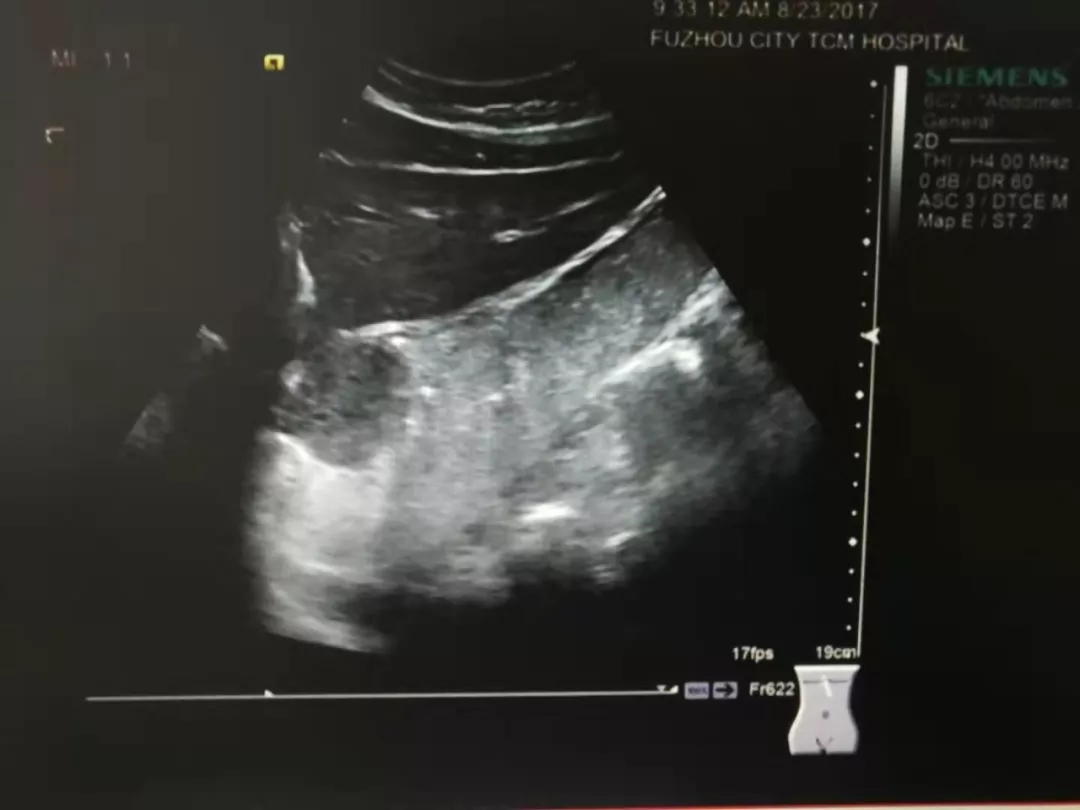

胃间质瘤